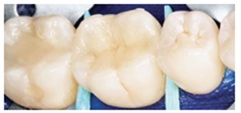

Просте виконання реставрацій бічної групи зубів Filtek™ Bulk Fill Flowable Restorative

Фото люб’язно надано Доктором Рейх, Зеефельд, Німеччина

Препарування зуба та внесення адгезиву 3M™ Single Bond™ Universal Adhesive.

Внесення матеріалу до 4 мм 3M™ Filtek™ Bulk Fill Flowable в підготовлену порожнину та полімеризація, наприклад 3M™ Elipar™ DeepCure-S LED

Перекриття 2 мм (мінімум) шаром естетичного композиту, наприклад 3M™ Filtek™ Universal та полімерізація.